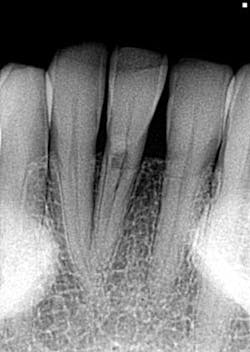

- Diagnosis given to the patient at the time lesion was first noticed: internal resorption. As you can see, a root canal was completed, but no changes noted to the lesion. Patient continued to have discomfort post root canal therapy (figure 6).

- Reassessment: external resorption confirmed by a 3-D scan. Tooth was recommended for removal and an implant was placed.